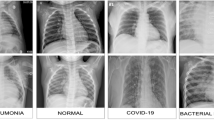

New potential for healthcare has been made possible by the development of the Internet of Medical Things (IoMT) with deep learning. This is applied for a broad range of applications. Normal medical devices together with sensors can gather important data when connected to the Internet, and deep learning uses this data to reveal symptoms and patterns and activate remote care. In recent years, the COVID-19 pandemic caused more mortality. Millions of people have been affected by this virus, and the number of infections is continually rising daily. To detect COVID-19, researchers attempt to utilize medical imaging and deep learning-based methods. Several methodologies were suggested utilizing chest X-ray (CXR) images for COVID-19 diagnosis. But these methodologies do not provide satisfactory accuracy. To overcome these drawbacks, a recalling-enhanced recurrent neural network optimized with golden eagle optimization algorithm (RERNN-GEO) is proposed in this paper. The intention of this work is to provide IoT-based deep learning method for the premature identification of COVID-19. This paradigm can be able to ease the workload of radiologists and medical specialists and also help with pandemic control. RERNN-GEO is a deep learning-based method; this is utilized in chest X-ray (CXR) images for COVID-19 diagnosis. Here, the Gray-Level Co-Occurrence Matrix (GLCM) window adaptive algorithm is used for extracting features to enable accurate diagnosis. By utilizing this algorithm, the proposed method attains better accuracy (33.84%, 28.93%, and 33.03%) and lower execution time (11.06%, 33.26%, and 23.33%) compared with the existing methods. This method can be capable of helping the clinician/radiologist to validate the initial assessment related to COVID-19.